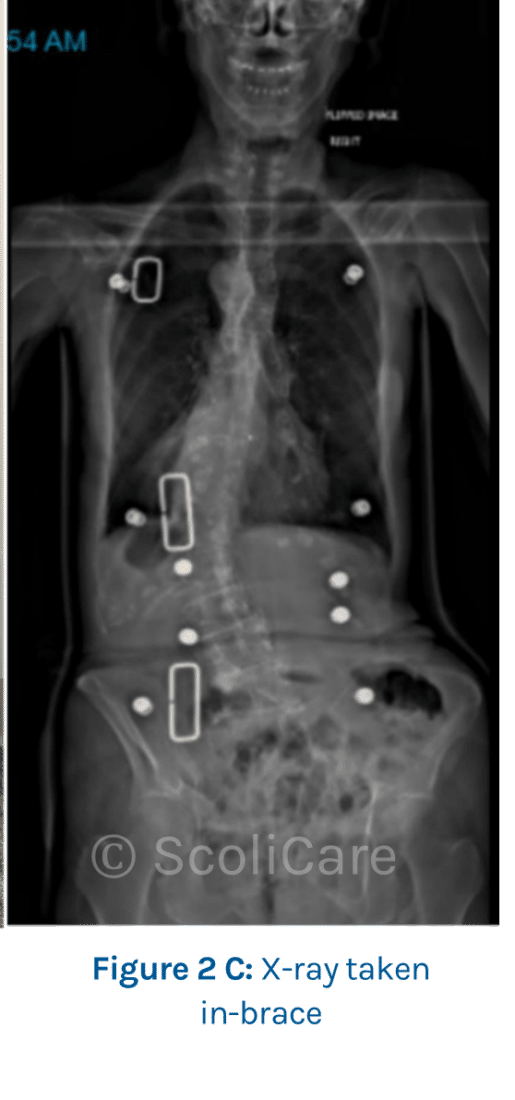

As the patient was diagnosed with a post-traumatic de novo degenerative scoliosis with unstable demonstrated progression, she was prescribed a custom-made scoliosis brace. X-ray taken in-brace shows curve improvement (Figure 2C).